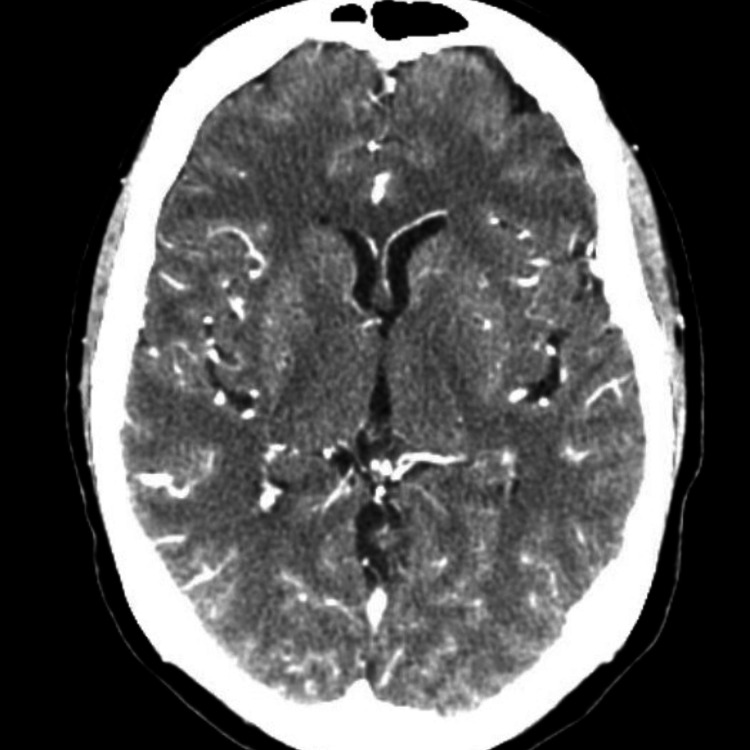

Our patient is a 60-year-old female with a past medical history significant for type II diabetes, dyslipidemia, major depressive disorder, osteoarthritis, rheumatoid arthritis, and chronic low back pain, current smoker (smokes about two to three packs per day) who was brought in by the family to our emergency department with complaints of fever and altered mental status. As per the family, the night before the presentation she had gone to bed complaining of headache, and right-sided ear pain. In the morning she was found to be altered, febrile, and nonverbal. They reported no trauma, no recent domestic or international travel, no rashes, no recent camping trips, and no pets at home. A quick review of her chart revealed that the patient had come to our emergency department multiple times in the two weeks preceding her current visit. She had first presented to the Emergency Department (ED) 11 days prior with complaints of bilateral frontal headache for five days. She did not have any meningeal signs on examination, however, she has right-sided ear effusion with a bulging tympanic membrane. Labs in this visit were significant for WBC 22,000 (4800-10800 K/µL), and C-reactive protein (CRP) 20.45 (<0.3 mg/dL). A CT head and CT angiogram of the head and neck were negative for any acute findings (Figure 1 and Figure 2).

Figure 1. CT angiography head with and without contrast: no acute findings.